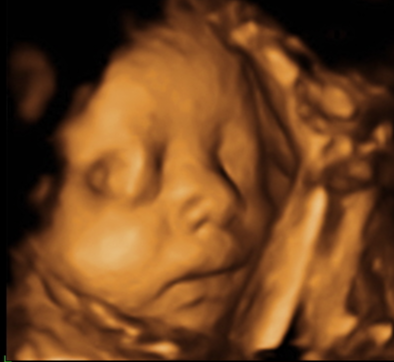

역아 였을 때 24주와 30주 입체 초음파 사진을 보면 얼굴옆에 다리가 있고 다리를 안고 있는 것 처럼 보였고 얼굴은 오른쪽 얼굴을 보였었는데